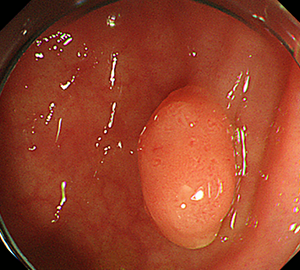

【大腸カメラからそのまま行えるポリープ切除】

当院では、大腸カメラで切除対象のポリープが見つかった際に、そのまま大腸ポリープ切除に切り替えて日帰りでの切除を行うことが可能となっております。

コールドスネアポリペクトミー(CSP)

合併症の非常に少ない優れた治療法であることから、近年大腸ポリープの外来切除法として急速に施行件数が増えてきています。当院ではこのコールドスネアポリペクトミーを主体としたポリープ切除を行っています。

| 3:病変をスネアに通します。 | 4:周囲の正常粘膜をしっかり入れながら、病変を絞扼していき... | |

| 5:切除します。切除検体は吸引回収し病理検査を行います。 | 6:切除後に洗浄・観察して、病変の遺残ががないことを確認します。 |